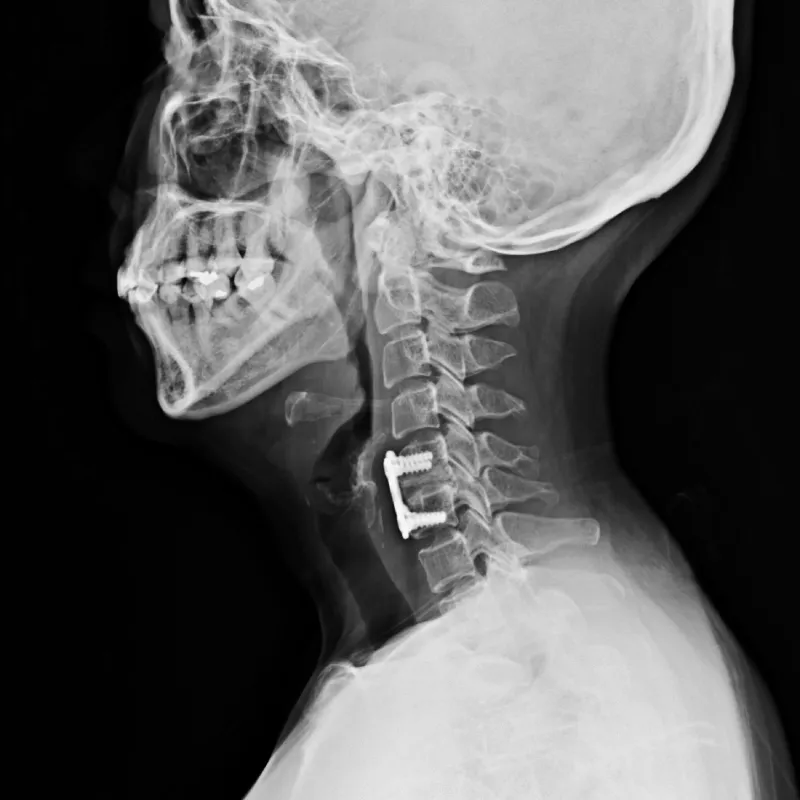

Anterior Cervical Discectomy And Fusion With Cage

Anterior Cervical Discectomy And Fusion With Plating

Anterior Cervical Discectomy And Fusion

C5/6 Anterior Cervical Discectomy And Fusion